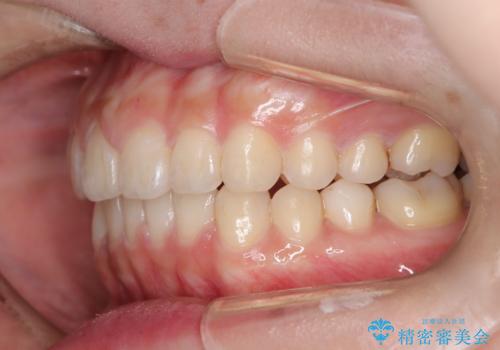

- 口元の突出感、歯のがたつきを主訴に来院された患者様です。非抜歯にて口元を下げるような治療計画を立案しました。非常に治療に対して真面目で協力的な患者様で、一緒に理想形を相談しながら治療を進めました。矯正前には、虫歯治療や親知らず抜歯を行っています。噛みしめ癖が強く、終盤は奥歯の噛み合わせのためにゴム掛けにご協力いただきました。